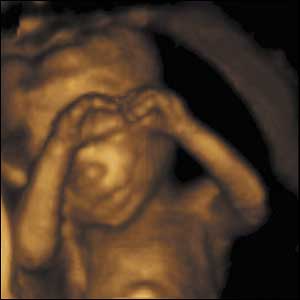

34 weeks gestation. 34cm from crown to rump.

8 of 10

While newborns do not smile until 4-6 weeks after birth, babies in the uterus do. Maybe because the uterus is warm, comfortable, and shielded from loud noise and bright light.